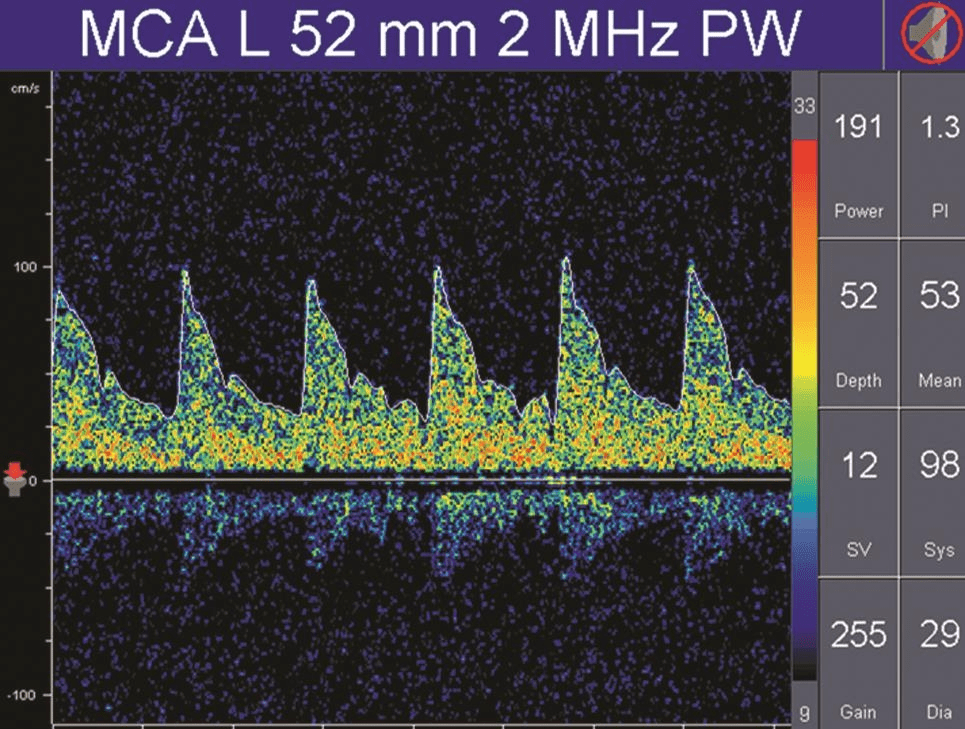

搏動指數(shù)(pulsatility index,PI)和阻力指數(shù)(resistant index,RI)是描述頻譜形態(tài)的參數(shù),通常是由血流速度計算出來,計算公式為:PI=(Vs-Vd) /Vm,RI=(Vs-Vd) /Vs。

PI值主要受收縮期和舒張期血流速度差的影響,差值越大,PI值越大;差值越小,PI值也越小。

因此,PI值可以反映血管內(nèi)血流壓力灌注情況或遠(yuǎn)端血管的阻力大小。

正常情況下顱內(nèi)血管的血流頻譜為相對低搏動性波形(PI值為0.55~1.05),而外周血管(顱外頸動脈或肢體血管)為相對高搏動性或高阻力波形(PI值通常大于1.05),顱內(nèi)正常搏動指數(shù)和阻力指數(shù)的頻譜(詳情見下圖)。